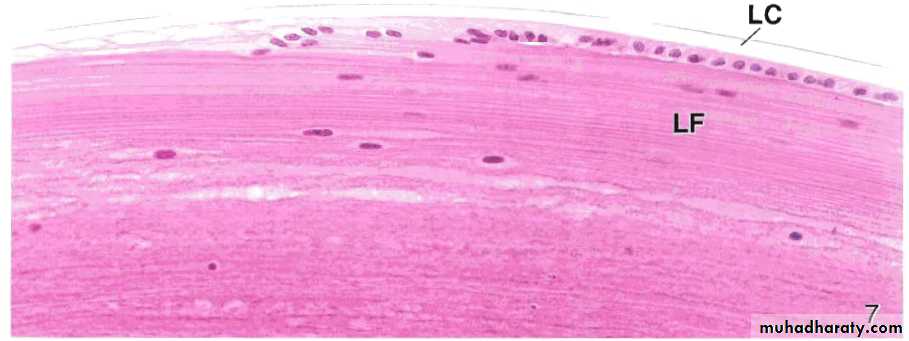

The lens

Transparent biconcave lies behind the irisAvascular and highly elastic to focus the light on the retina

Composed of capsule, epithelium and fibers

The ciliary zonule lie between the lens and the ciliary body, holds the lens in position and important for the accommodation

When ciliary muscles contract, the zonule is relieved and the lens become thicker and round up, and vice versa

A photomicrograph of the lens near its equator, LC. Lens capsule,LF. Lens fibers